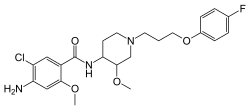

Antiemetika

Als Antiemetika zur Behandlung von Übelkeit und Erbrechen werden Setrone wie Ondansetron, Granisetron, Tropisetron und Palonosetron eingesetzt. Ihre größte Wirksamkeit zeigen sie bei der Behandlung des akuten Erbrechens nach einer Chemotherapie von Tumorerkrankungen mit mäßig oder hochgradig brechreizauslösenden Zytostatika wie beispielsweise Cisplatin. Die Kombinationstherapie von Palonosetron mit dem Glucocorticoid Dexamethason ist darüber hinaus beim verzögerten Zytostatikaerbrechen erfolgversprechend.[94] Des Weiteren kommen sie bei der Therapie von postoperativer Übelkeit und Erbrechen zum Einsatz.[95]

Ihre Wirksamkeit verdanken die Setrone einer Hemmung der Serotoninwirkung an 5-HT3-Rezeptoren, die sowohl im Darmnervensystem als auch im Brechzentrum des Hirnstammes in besonders hoher Dichte zu finden sind. Auch die brechreizhemmende Wirkung von Metoclopramid beruht zumindest zum Teil auf einer antagonistischen Wirkung auf diese Rezeptoren.[96] Der 5-HT3-Rezeptorantagonist Alosetron findet darüber hinaus in der Behandlung des Reizdarmsyndroms Anwendung.[97]